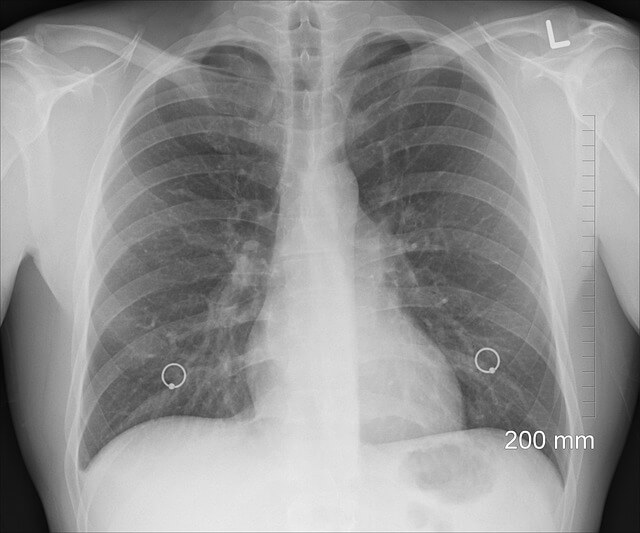

폐에 물이 차는 증상은 폐수종(Pulmonary edema) 또는 흉수(Pleural effusion)로 불리며, 폐나 폐를 둘러싼 흉막 공간에 과도한 체액이 축적되는 현상을 말합니다. 이는 심장 질환, 신장 질환, 감염 등 다양한 원인에 의해 발생할 수 있습니다.

폐에 물이 차면 초기에는 경미한 증상이지만, 시간이 지날수록 호흡곤란이 심해지고 생명에 위협이 될 수 있습니다. 다음과 같은 증상이 있다면 주의해야 합니다.

- 숨이 차고 호흡이 어려움 - 가벼운 활동 시에도 숨이 차거나, 누우면 더욱 악화됨

- 가슴 답답함 및 흉통 - 폐와 주변 조직에 물이 차면서 가슴이 답답하게 느껴짐

- 기침 및 거품 섞인 가래 - 흰색 또는 분홍색 거품이 섞인 가래가 나올 수 있음

- 손발이 차고 피부가 창백함 - 혈액순환이 원활하지 않아 발생

- 야간에 심해지는 증상 - 밤에 증상이 악화되어 수면 장애를 유발할 수 있음